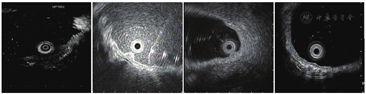

20例病例中有4例完成了超声内镜检查,与其他类型胃癌有相同之处,也有不同之处。GA-FG在超声下表现为低回声占位性病变,似起源于黏膜肌层,肿瘤浅层仍保留有较为完整的高回声黏膜层,病变主体向下生长,与黏膜下层分层欠清,固有肌层完整(图3)。

注:自左向右病例编号为1、2、5、20。